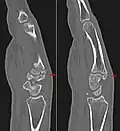

Carpal boss in der seitlichen Röntgenaufnahme der Handwurzel. -